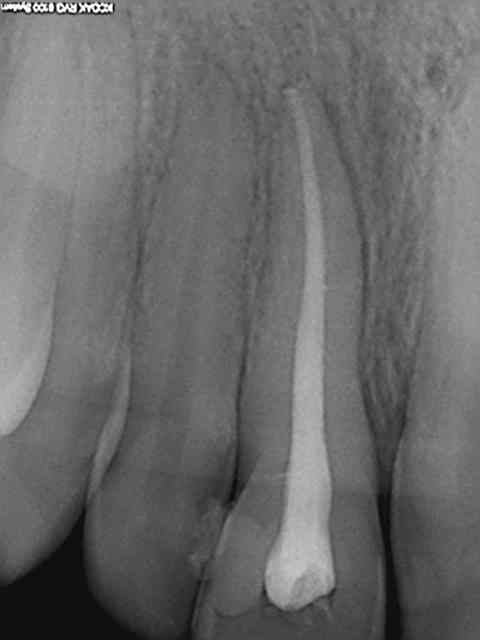

Radio initiale, cone en place , cone scellé, radio du bouchon apical réalisé au système b, puis radio finale après thermo-condensation. C'est obligatoire avec la nouvelle CCAM. Fini de jouer au dentiste le 1er juin.)))))))

Elles sont dans le désordre , remets les en ordre ( ca fait partie d'un qcm de formation continue) vu que le niveau de la formation initiale semble resté bloqué dans les années 80.